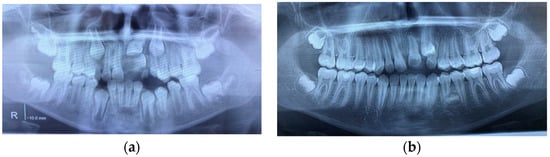

Figure 3.

(a) Impacted upper left central incisor blocked by a DC surrounding its crown and a supernumerary tooth. (b) Abnormal shape of the canine, root DL of the upper left central incisor, and a new tooth bud developing in the lower arch.

The objective of the orthodontic treatment was to preserve all the permanent teeth, as the replacement of any frontal teeth is very challenging despite the successful techniques in periodontology and implantology. The treatment started with surgery, including extraction of the supernumerary tooth and marsupialization of its DCs. A removable appliance was worn to maintain the space and eventually for orthodontic traction of the impacted teeth. The eruption process of the central incisor was monitored periodically by X-ray exams, and it was found that the central incisor erupted very slowly, with a tendency for impaction, and the decision was made to apply orthodontic traction to bring it into the oral cavity. At the same time, the canine changed its eruption path in a mesial direction, in transposition with the lateral incisor. The abnormal shape of the canine, with a big cingulum, like a supernumerary cusp, root DL of the central incisors and a new tooth bud between left mandibular premolars (Figure 3b), could be seen on the panoramic X-ray. In this clinical case, the root DL was seen only in the impacted central incisor associated with the DC, and the cause of DL could be the lack of space for the root to develop in a normal direction. This case is another case of dental anomaly pattern (DAP) or associated dental anomaly (ADA)—macrodontia, impaction, supernumerary teeth, DL and DC, transposition, an early eruption of permanent teeth, and DL might also have a genetic origin.

Figure 4.

(a) Initial panoramic X-ray revealed large DCs on both sides of the mandible. (b) CBCT image showing the labiolingual orientation of the lower left first and second premolars. (c) CBCT showing root DL of the left first premolar.

A lingual arch was placed to maintain the position of the first mandibular molars. Extraction of deciduous mandibular molars and the marsupialization of the cysts were performed. After surgery, all impacted teeth started their eruption in an appropriate position. Although the left first premolar changed its position to a normal one, there was not enough space for its eruption in addition to having a root DL (Figure 4c).